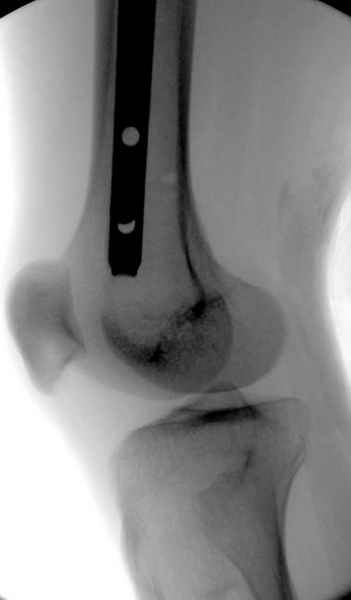

Больной долго оставался нестабильным, только на 14 день удалось заменить на антеградный интромедуллярный штифт TFN (trochanteric femoral nail) SmithNephew. После неудачной попытки закрытой репозиции, несмотря на использование "joystick", проксимальный стержень от

наружного фиксатора, (перелом начал срастаться) репозицию провели из малого доступа, затем остальные этапы операции.

Случай был представлен из-за того, что больного оперировали после наружной фиксации и был риск инфекцирования через места проведения стержней (на снимках), прошло больше 3 месяцев, выписан из амбулаторной службы из-за отсутсвия надобности дальнейшего наблюдения.